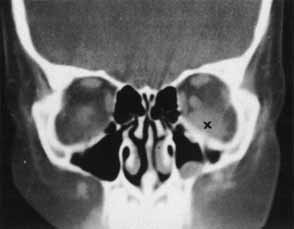

Traumatic optic neuropathy is estimated to occur in 4% of midfacial, supraorbital, or frontal sinus fractures1 and, therefore, should be suspected when there is decreased vision following orbital trauma in absence of globe injury. There will be a relative afferent papillary defect and evidence of orbital soft tissue injury. Visual acuity, afferent pupillary defects, visual fields, and color vision should be ascertained when possible. When damage occurs in the intraorbital portion of the optic nerve, the appearance of the fundus may resemble a central retinal artery or vein occlusion and vitreous, subhyaloid, or retinal hemorrhages may be found radiating from the optic disc.3,4 However, with more posterior damage, the optic disc acutely may appear normal. An orbital CT scan should be obtained with axial and coronal views to assess the integrity of the optic nerve and the presence of an optic nerve sheath hematoma, orbital hemorrhage, or fracture (Fig. 1). The radiologic finding of optic canal fractures may be subtle, and blood in the posterior ethmoid sinus may be the only indication of a fracture with intracanalicular extension.

Fig. 1 CT scan of a fragment of bone extending into the optic canal (arrow).